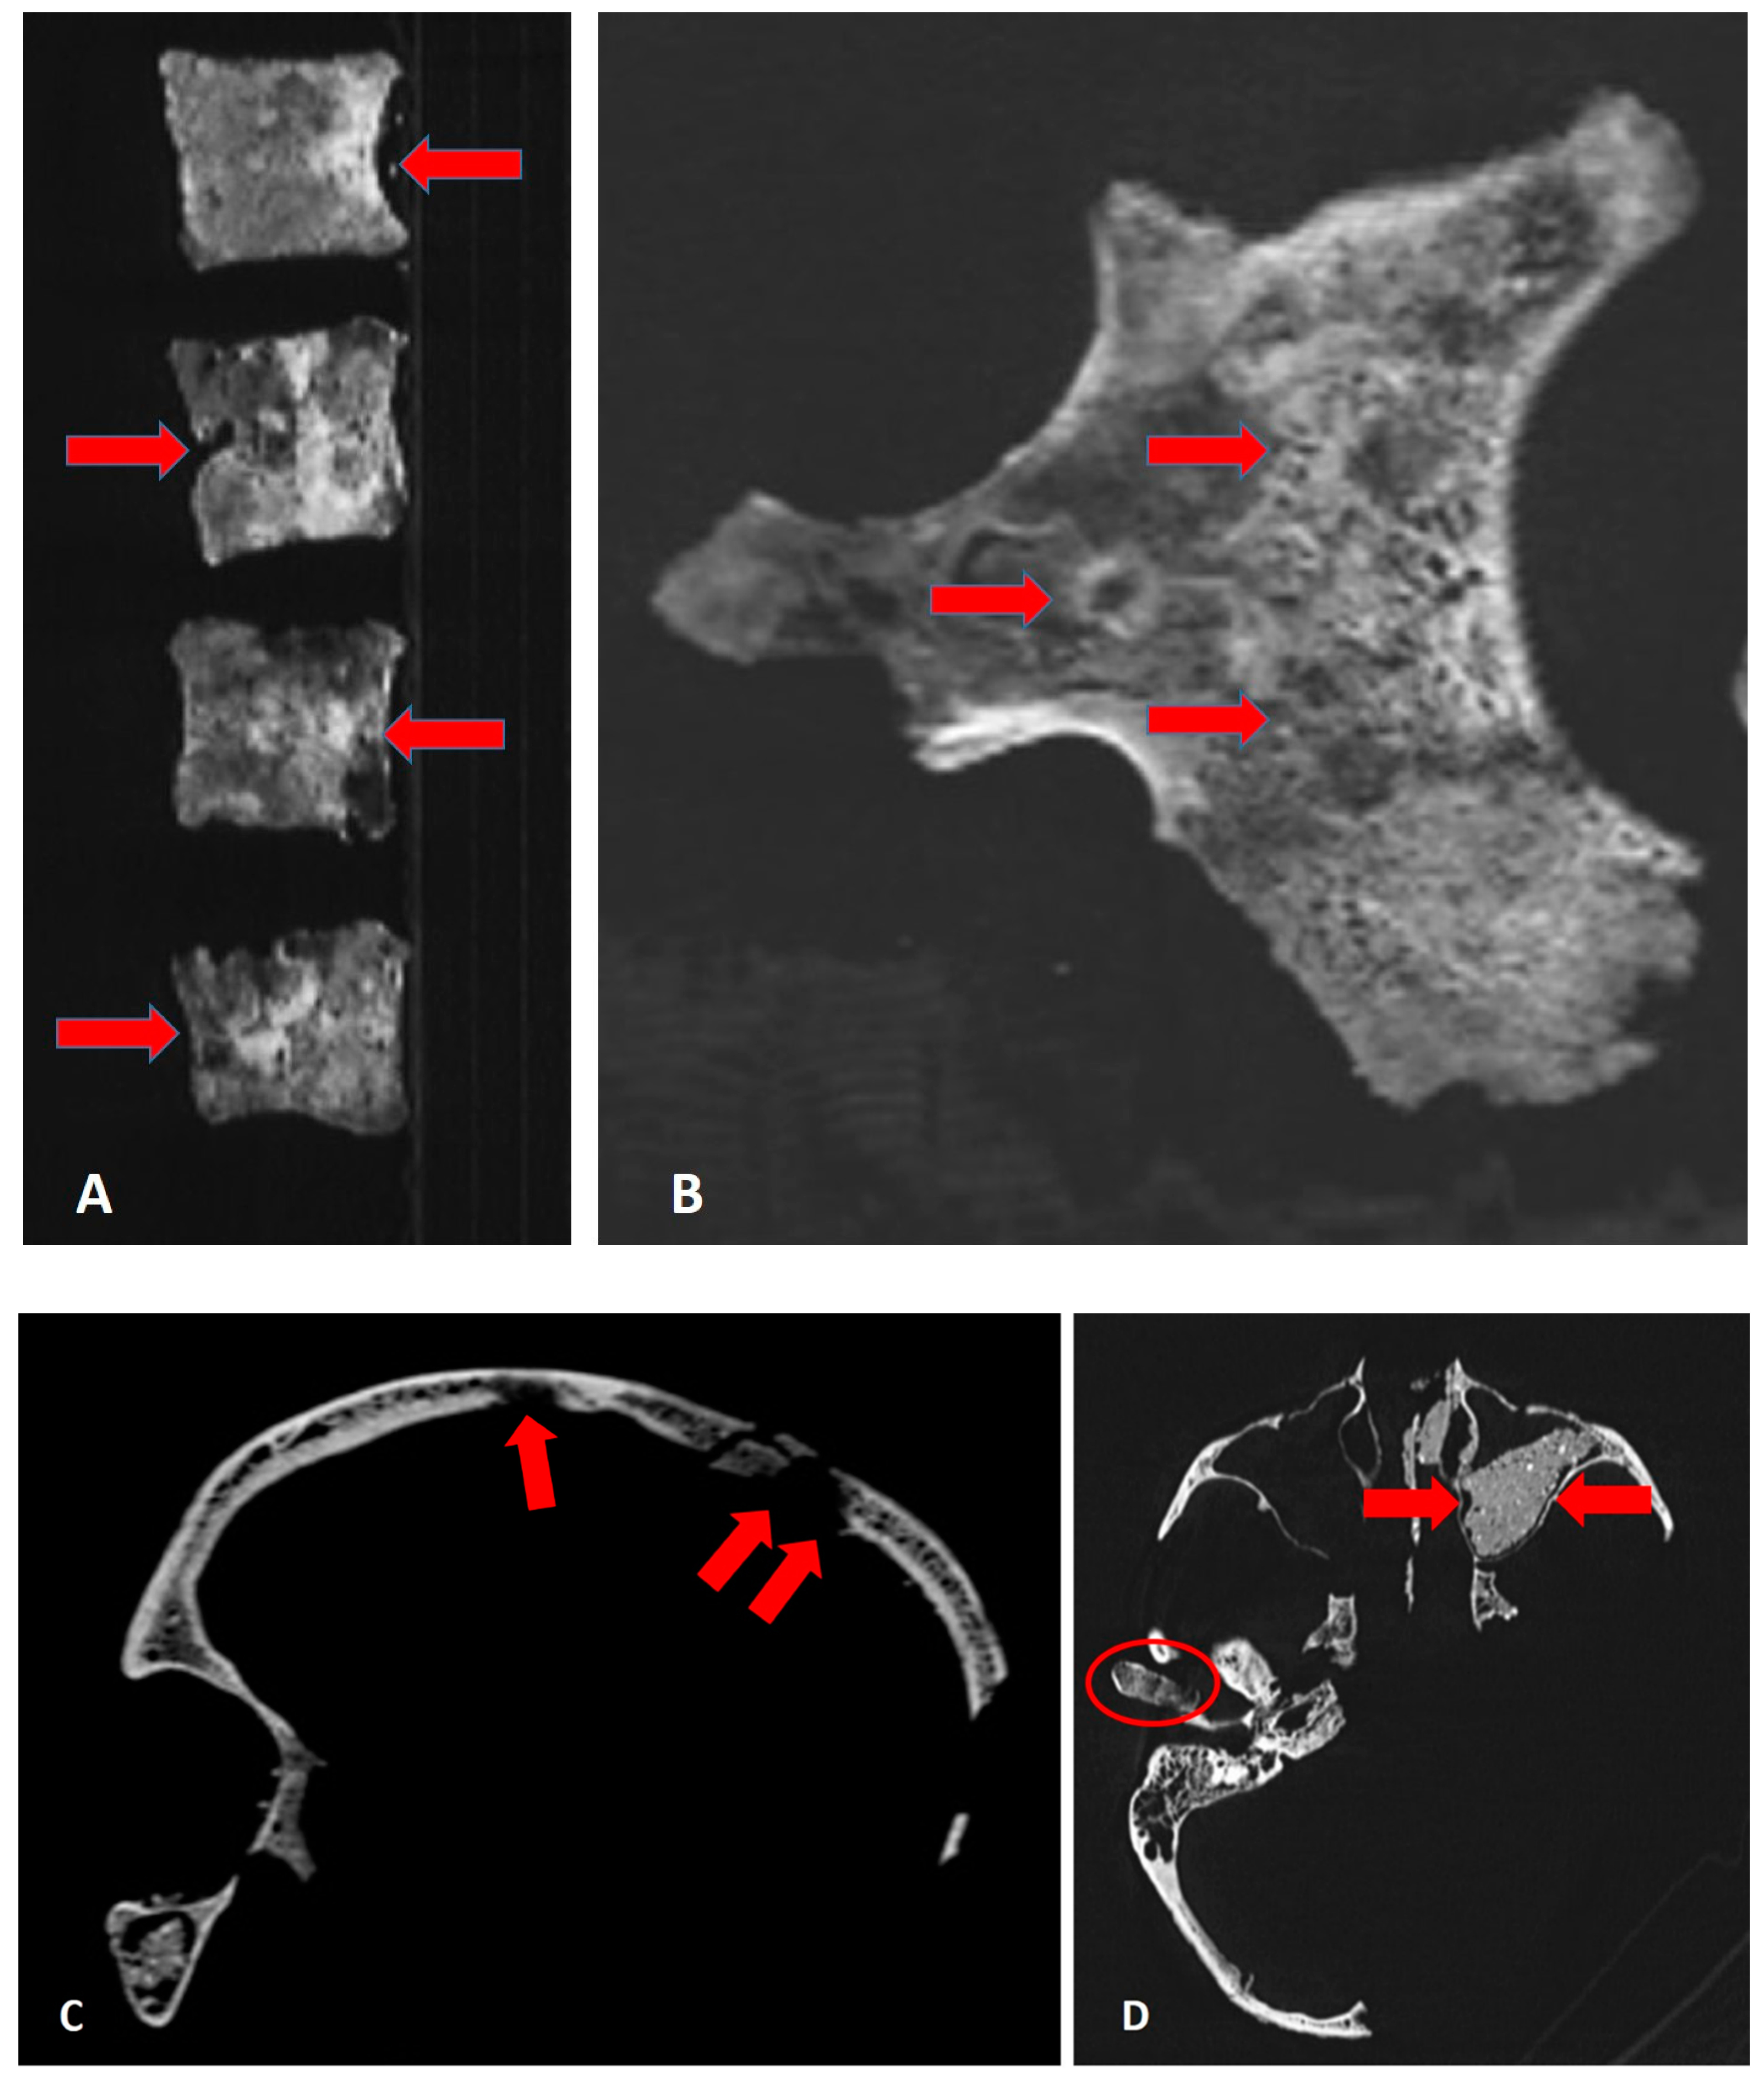

3.2. Palaeopathological Analysis

3.3. CT Scans